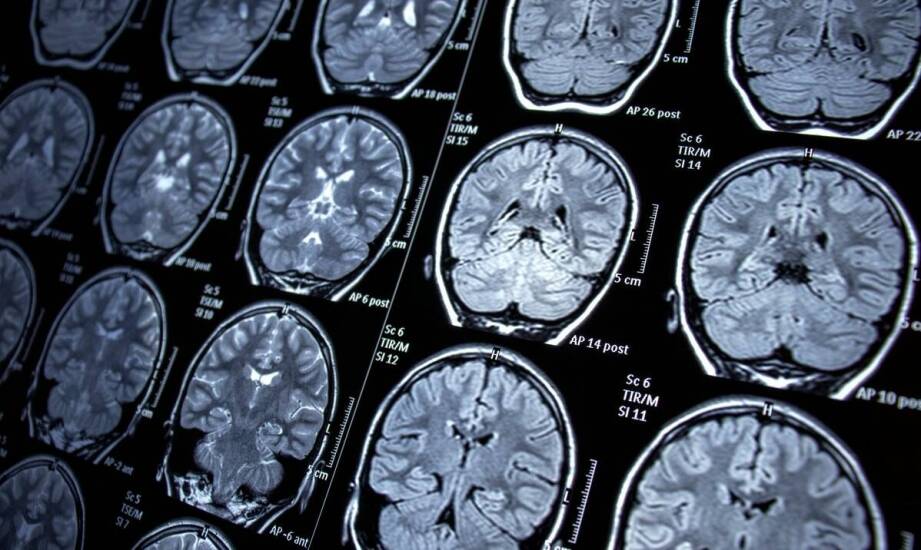

Guz przysadki mózgowej to schorzenie, które wpływa na zdrowie pacjentów. Jacek Kunicki - Prywatna Praktyka Lekarska podkreśla znaczenie zrozumienia tej choroby oraz jej objawów guza przysadki mózgowej. Właściwe rozpoznanie umożliwia skuteczne leczenie i monitorowanie jakości życia. Regularne badania kontrolne są kluczowe w ocenie stanu zdrowia oraz reakcji na zmiany w symptomach. Dzięki nim można unikać poważnych komplikacji zdrowotnych. Edukacja na temat guza przysadki mózgowej oraz znaczenia badań kontrolnych jest istotna dla samopoczucia i zdrowia psychicznego pacjentów. Zrozumienie objawów oraz ich wpływu na codzienne życie może wspierać zarządzanie chorobą i wprowadzenie zmian w stylu życia.

Objawy związane z guzem przysadki mózgowej mogą być różnorodne i oddziaływać na codzienne życie chorych. Bóle głowy, problemy z widzeniem czy zmiany hormonalne to tylko niektóre z nich. Bóle głowy mogą być przewlekłe i silne, co prowadzi do chronicznego zmęczenia. Problemy ze wzrokiem, takie jak podwójne widzenie czy utrata ostrości, wpływają na bezpieczeństwo osób w codziennych sytuacjach. Zmiany hormonalne mogą powodować trudności z nastrojem oraz obniżone libido. Objawy guza przysadki mózgowej mają znaczący wpływ na jakość życia pacjentów, dlatego istotne jest szybkie rozpoznanie i leczenie schorzenia oraz regularne badania kontrolne. Edukacja chorych oraz wsparcie dla nich i ich rodzin są kluczowe w radzeniu sobie z trudnościami związanymi z tym guzowatym schorzeniem. Wsparcie to może obejmować grupy wsparcia, terapie indywidualne oraz dostęp do informacji o chorobie, co pozwala lepiej zrozumieć swoje objawy.

Ustępowanie objawów związanych z guzem przysadki mózgowej jest zjawiskiem rzadkim, jednak zdarzają się sytuacje, w których symptomy mogą ulegać złagodzeniu. Może to być spowodowane różnymi czynnikami, takimi jak zmiany hormonalne, styl życia czy terapia. Niektórzy pacjenci doświadczają poprawy po wprowadzeniu modyfikacji w diecie, aktywności fizycznej czy redukcji stresu. Należy jednak pamiętać, że ustąpienie objawów nie oznacza wyleczenia. Guz przysadki mózgowej może nadal być obecny i prowadzić do dalszych komplikacji, dlatego osoby chore powinny kontynuować regularne badania kontrolne. Dzięki temu lekarze mogą szybko reagować na ewentualne pogorszenie symptomów. Objawy związane z guzem przysadki mózgowej mogą być różnorodne, a ich monitorowanie jest kluczowe. Jacek Kunicki - Prywatna Praktyka Lekarska, specjalizująca się w diagnozowaniu oraz terapii guzów przysadki mózgowej, oferuje wsparcie dla pacjentów oraz ich bliskich. Szkolenie dotyczące choroby oraz roli badań kontrolnych przyczynia się do lepszego zrozumienia stanu zdrowia i umożliwia podejmowanie świadomych decyzji dotyczących leczenia. Każdy przypadek jest inny, a indywidualne podejście do pacjenta ma kluczowe znaczenie w procesie terapeutycznym.